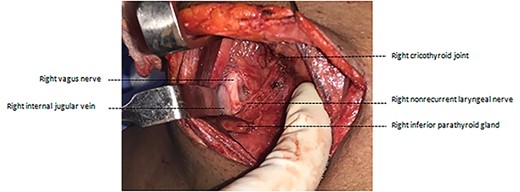

A preoperative magnetic resonance imaging (MRI) of the neck (Fig. 2) showed enlarged left lobe of thyroid with a solid nodule of 3.1 × 3.0 × 2.3 cm with mild mass effect on trachea. In addition, an aberrant right subclavian artery, taking a retro-esophageal, retro-tracheal course to the right upper limb was detected.

MRI with contrast showing right aberrant subclavian artery taking turn behind the trachea and esophagus.